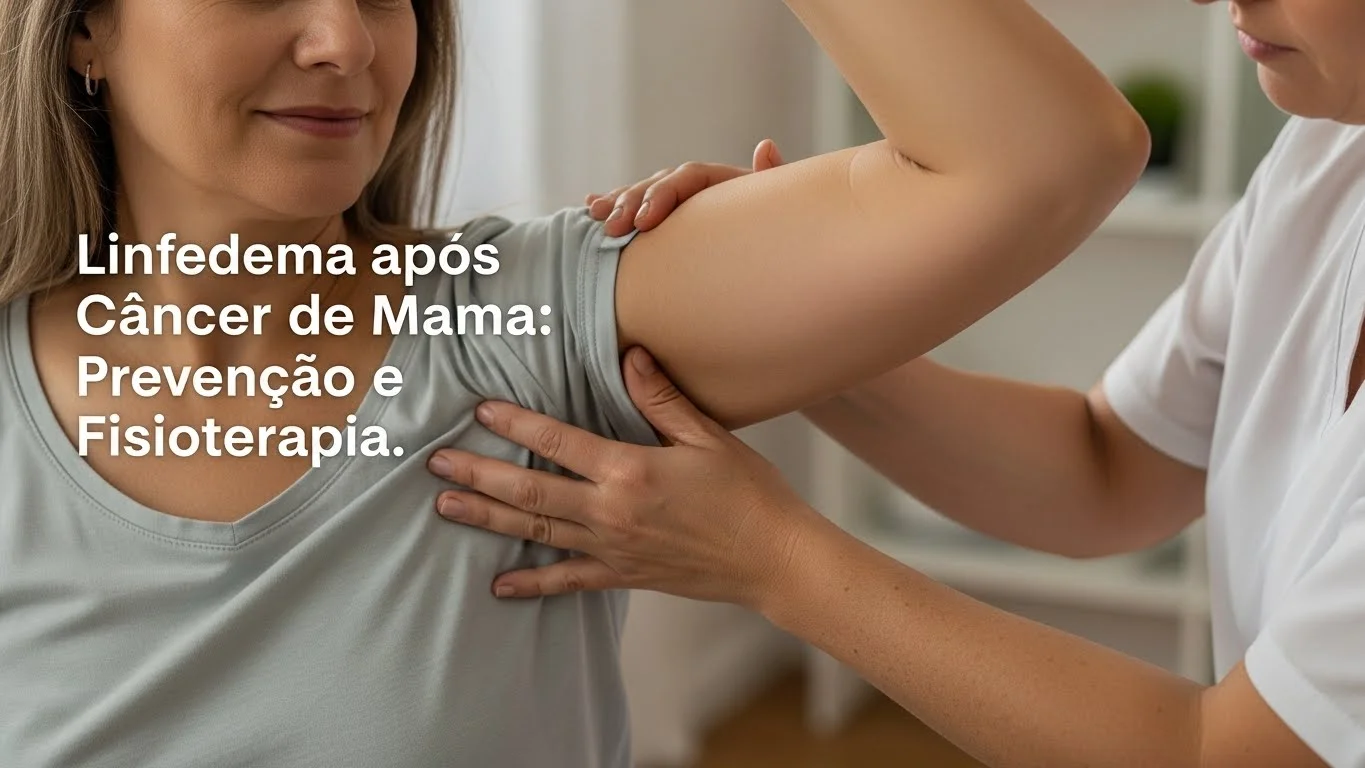

Linfedema após Câncer de Mama: prevenção e fisioterapia O linfedema é o inchaço do braço e/ou mão após o tratamento...